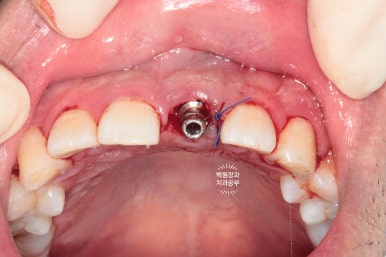

잘 위치된 임플란트 고정체 (fixture)에 임시 지대주를 연결해줍니다.

임시 지대주의 크기는 정해져 있기 때문에, 구강 내 상황은 환자마다 다르므로 그 형태를 다듬어 주어야 합니다.

임시 지대주의 길이를 짧게 다듬어 아래 앞니에 닿지 않는 것을 확인하고,

그 내부를 임시 재료로 메꿔준 다음에

준비해두었던 임시치아를 연결해주게 됩니다.

뒷 부분을 하늘색 임시재료로 메꿔드렸고,

환자분은 왼쪽 상태로 귀가하실 수 있었습니다.